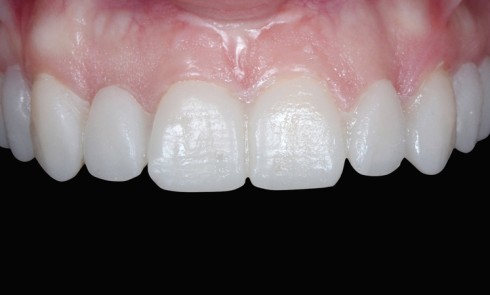

Article réservé à nos abonnés Projet prothetique et utilisation du mock-up : des facettes à l’implantologie

De tout temps, l’homme a voulu modifier son aspect physique pour gagner en confiance et offrir une meilleure image de...